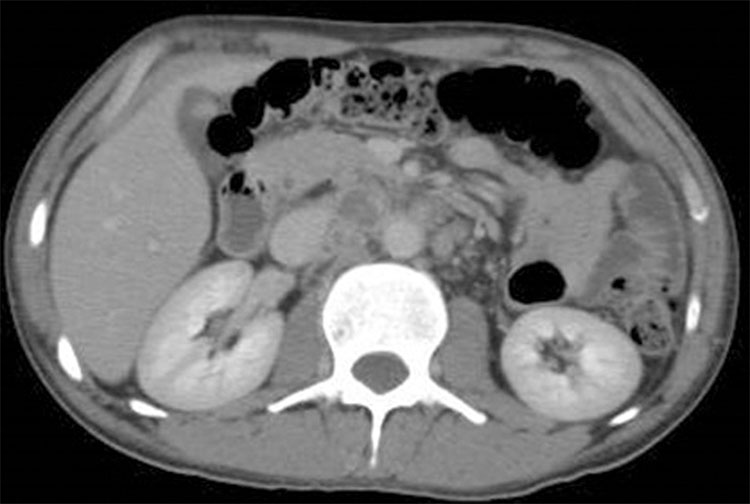

La alteración más precoz se aprecia a nivel de los cálices con erosiones en "apolillado". Ese hallazgo es seguido de una necrosis papilar. Se puede observar una falla renal y una dilatación del sistema pielocaliciliar (Fig. 4). Hallazgos como cavitaciones del parénquima renal o bien cicatrices fibróticas del parénquima se aprecian en estados más avanzados. Calcificaciones con distribución lobar se observan en estadios finales.8 Lesiones similares se pueden encontrar en pielonefritis xantogranulomatosa.

Mujer de 44 años con antecedentes de TBC pulmonar, pleural y genitourinaria, nefrectomizada derecha, enfermedad renal crónica en hemodiálisis, realizó una consulta por dolor abdominal y crisis hipertensiva secundaria. (a y b) Se realizó TC que destacó una marcada dilatación del sistema caliciliar con destrucción caseosa corticalocorticomedular y delparénquimarenal. (c) Se realizóuna reconstrucción de TC en 3D que destacó con mayor énfasis las dilataciones mencionadas. En el examen de orina se aislaron bacilos de Mycobacterium tuberculosis.